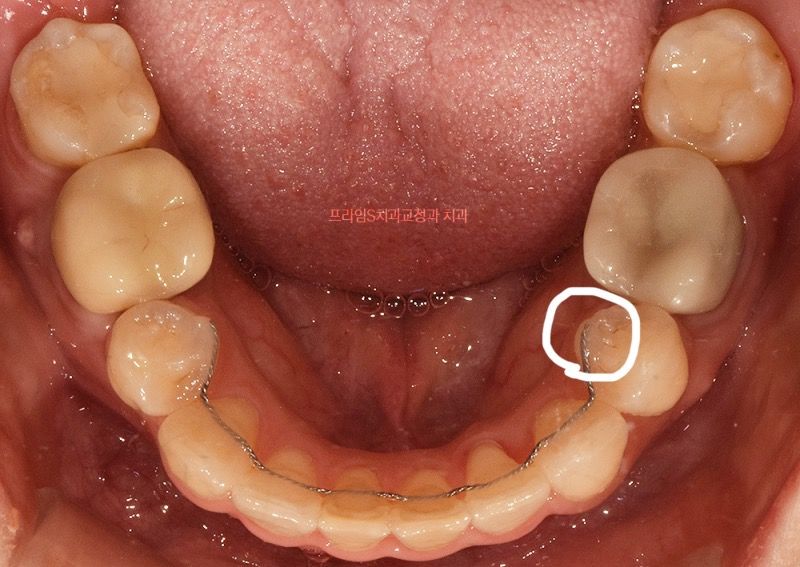

떨어진 유지장치 잘라도 되나요???

동그라미 친 부분이 붙여도 자꾸 떨어져서 너무 스트레스 받아요ㅠ

크게 문제되지 않으면 떨어진 쪽을 아예 잘라버리고 싶은데 괜찮나요??

• 1번 째 사진

3,4번 사이는 저작시 교합력 방향이 달라서 잘 떨어집니다 자르면 그쪽은 치아 이동이 시작될 수 있습니다